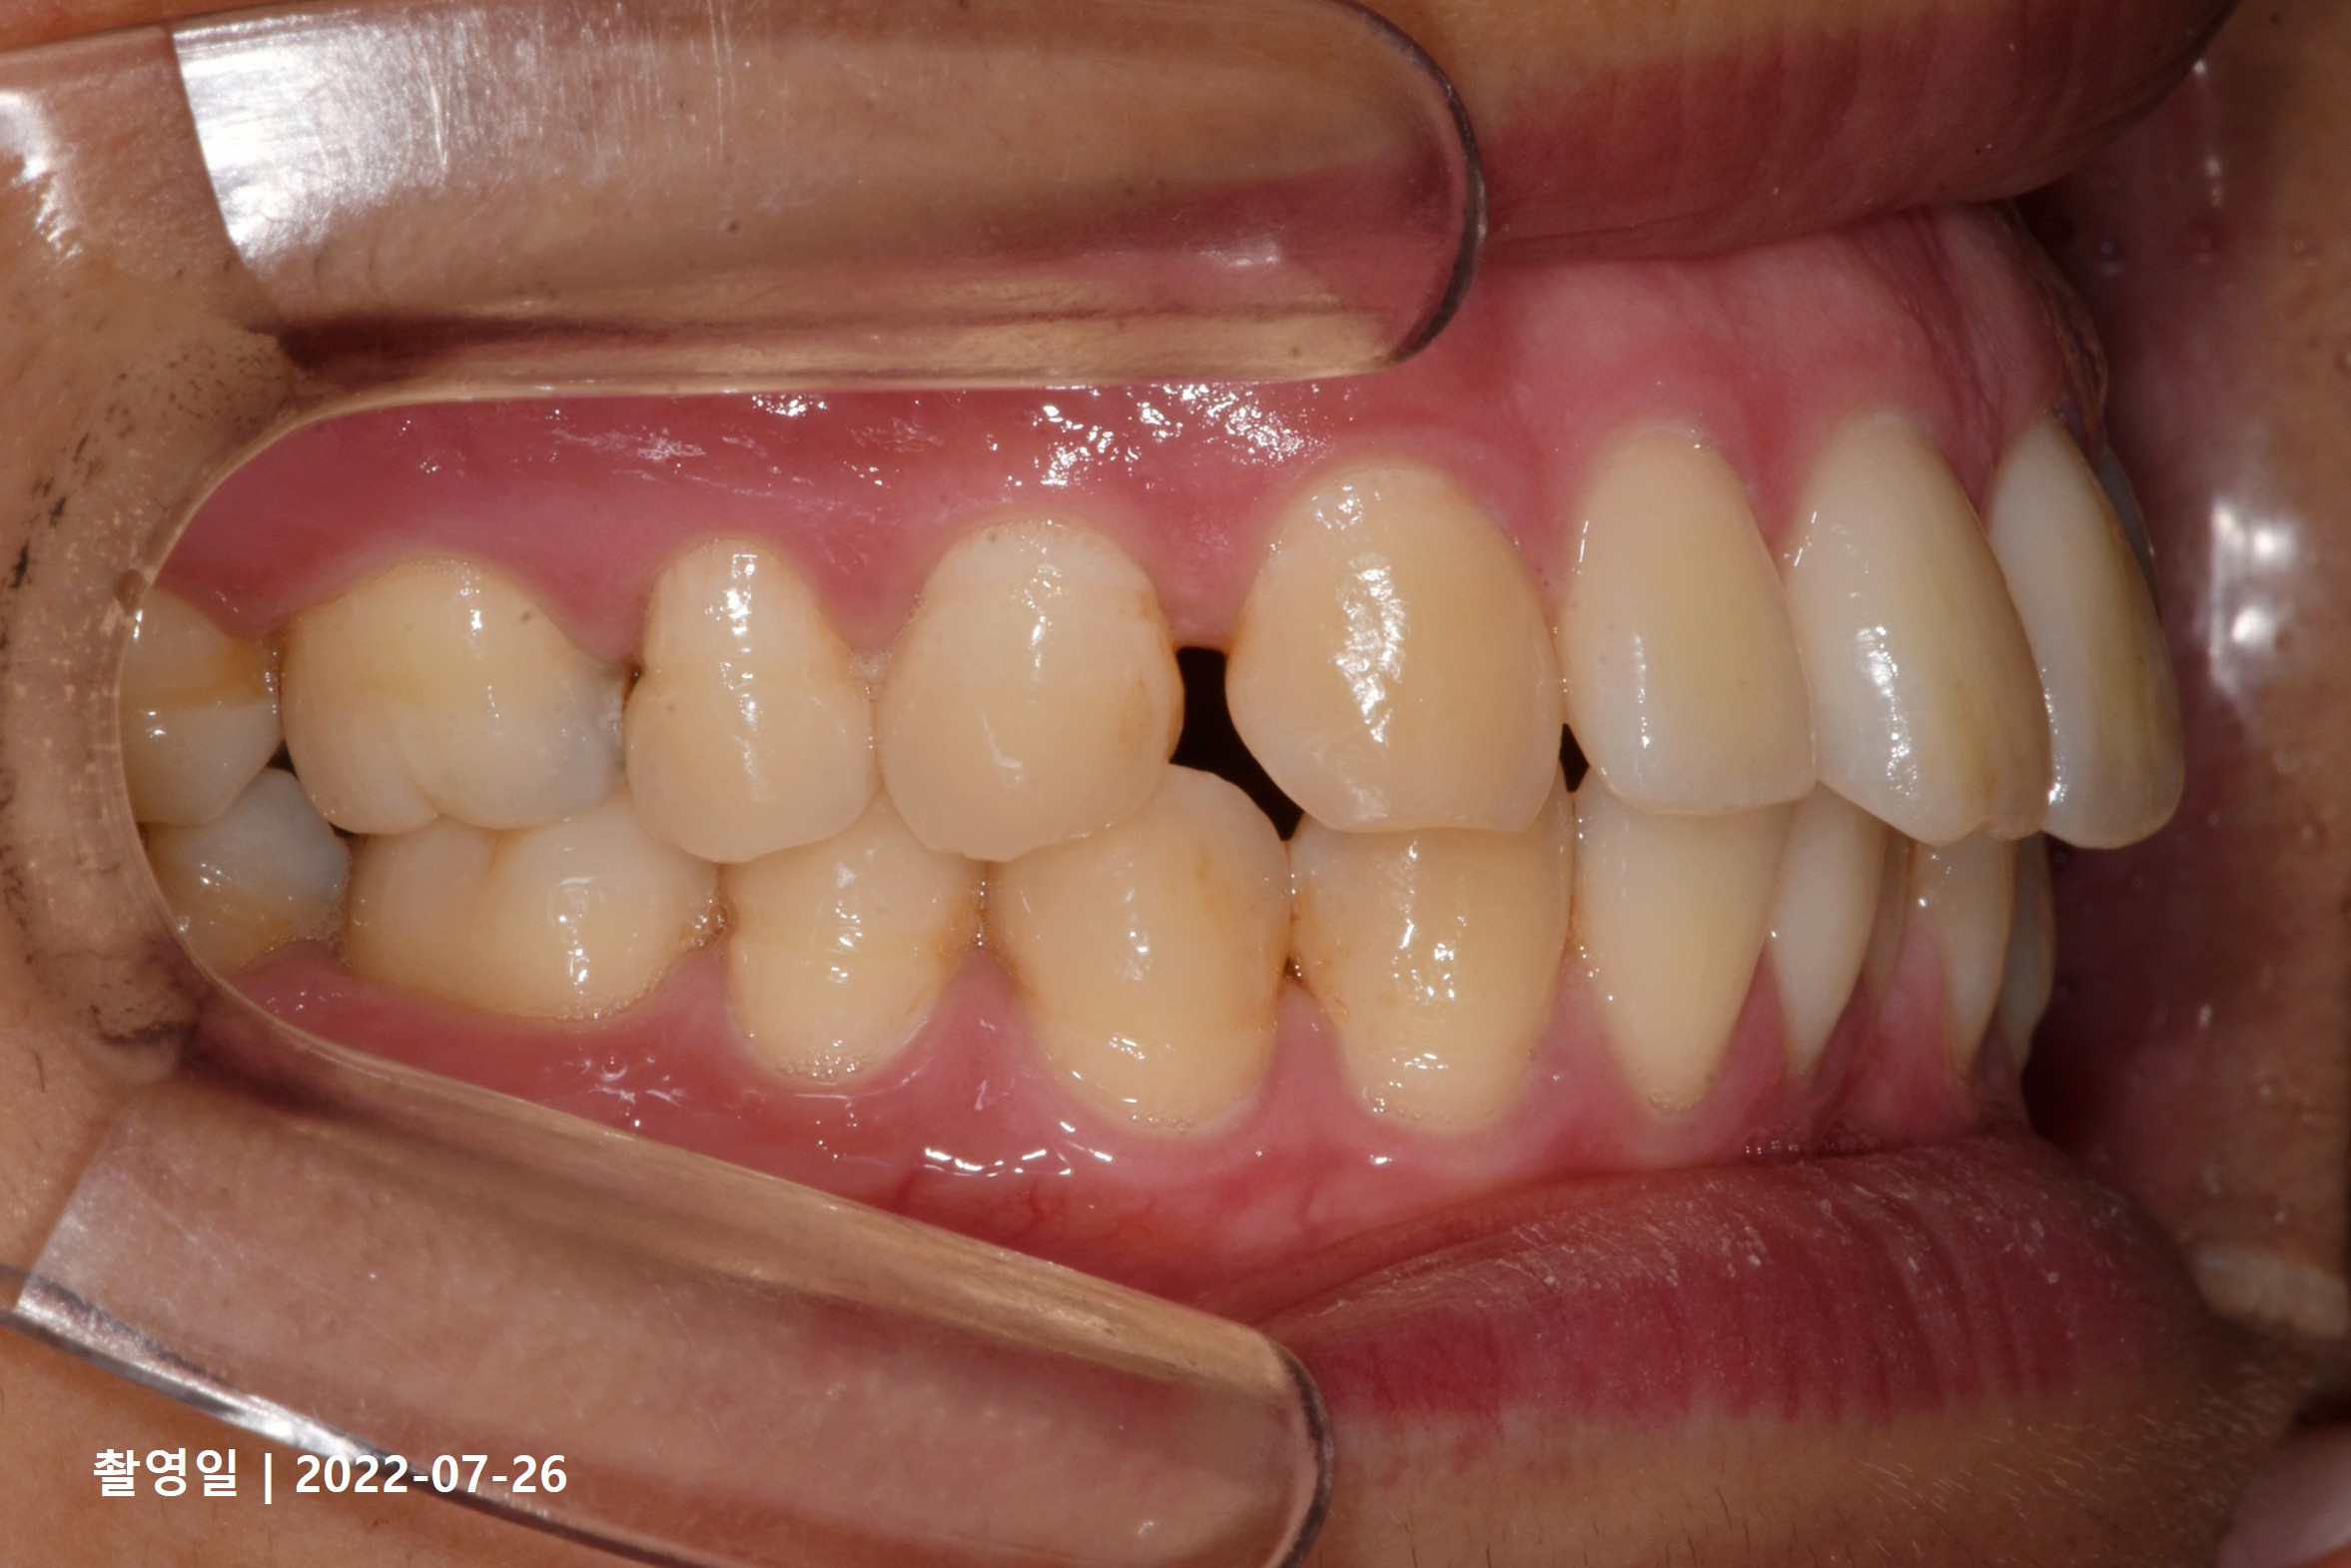

Case 4

- 19세 여성

- 상하악소구치 발치

- 치료기간 2년 8개월

치료 전

치료 후